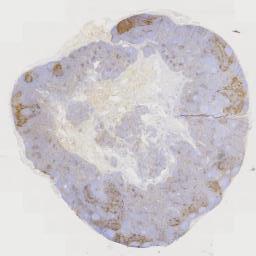

大体所见: 灰红组织一块,大小为6*4.5*2.5cm,表面灰红,切面灰白,质韧。

免疫组化: CK(pan)(+),EMA(灶+),S-100(+),P63(个别+),CK7(-),GFAP(-),SOX-10(-),CD34(血管+),CD117(-),Desmin(-),SMA(-),p53(+,野生型),p16(-),SATB2(-),Calponin(-),CDK-4(-),MDM2(-),INI-1(未缺失),Ki-67(约5%)。